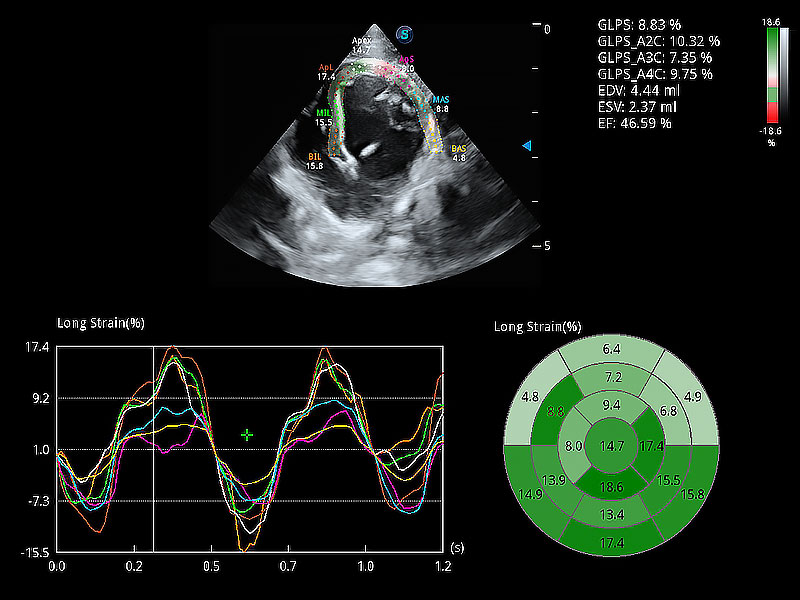

通過心肌識別技術(shù)與二維斑點(diǎn)追蹤技術(shù)相結(jié)合,對心臟的超聲圖像進(jìn)行量化分析。計算心肌17個節(jié)段的應(yīng)變、應(yīng)變率、速度、位移等,并通過牛眼圖的形式進(jìn)行呈現(xiàn)。

能夠基于左心室壁追蹤和辛普森法,自動計算射血分?jǐn)?shù),支持多個可移動點(diǎn)描跡,與手動測量相比,極大節(jié)省了動物醫(yī)生的時間和精力。